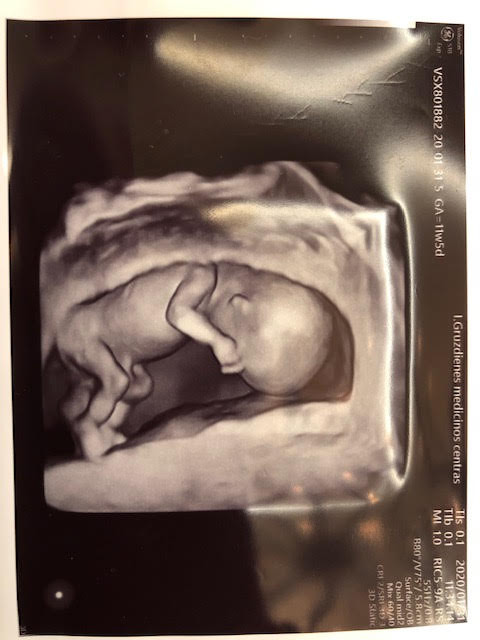

Mūsų medicinos centro tikslas, kad kuo daugiau besilaukiančių moterų turėtų galimybę atlikti pačius tiksliausius genetinius tyrimus, dėl dažniausiai pasitaikančių genetinių sindromų, kurie nustatomi atliekant neinvazinius prenatalinius tyrimus - NIPT, NIPT PLUS ( išplėstinis ). Pavykus sudaryti palankias sutartis su laboratorijomis, mūsų klinikos nėštukėms galime pasiūlyti palankiausią tyrimo kainą ir trukmę Lietuvoje!